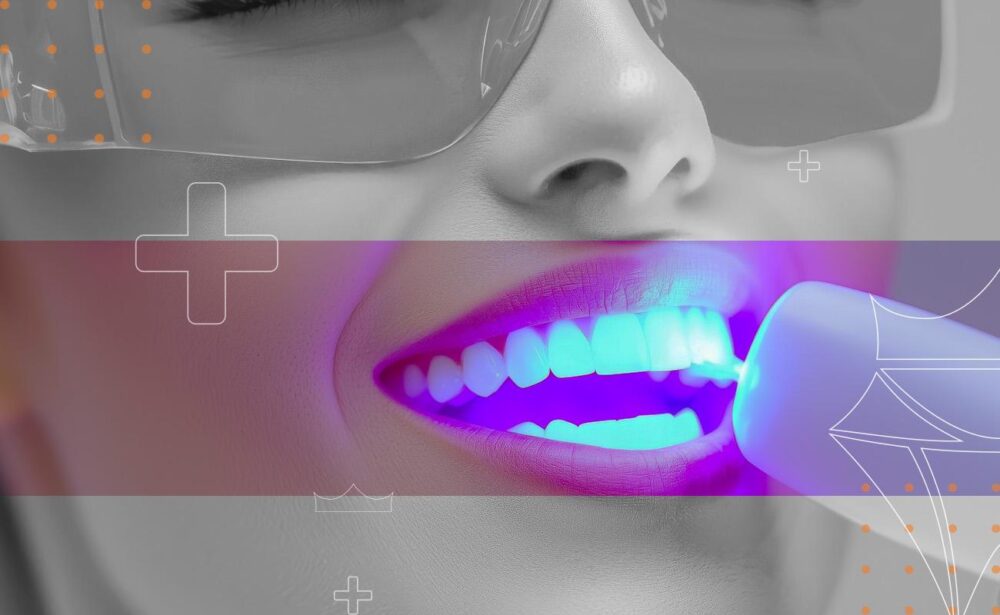

Laser Dentistry

Clover Medical Centre utilizes the Biolase Epic 10, the latest offering from BIOLASE (a market leader in the field of dental lasers for the past 25 year). While all diode lasers cut tissue using heat, many of them can increase tissue temperature excessively, causing patient discomfort. The Epic 10 keeps patients more comfortable two ways. Its 940 nm wavelength, developed exclusively for dentistry by Biolase, is better absorbed by hemoglobin and oxyhemoglobin than other wavelengths, so the Epic 10 cuts efficiently at lower power and with less heat.This unique combination of features means you can perform most laser procedures using topical anesthetic only. The EPIC 10® diode soft-tissue laser platform from BIOLASE Inc, Irvine, Calif, recently won the gold medal for Dental Instruments, Equipment, and Supplies at the 15th Annual Medical Design Excellence Awards (MDEA). Soft-tissue Surgery The Epic 10 offers the most precise control of tissue cutting for different procedures and tissue biotypes. The soft tissue applications include gum surgery. Gum re-contouring, de-pigmentation, pocket therapy, endodontic disinfection, abscess treatment, frenectomy and minor gingival surgical procedures. The Epic 10 uses better bendable tips for better access to all areas, and offers single-use disposable tips for quick, convenient treatment, and improved cleanliness. Temporary Pain Therapy and Relief The Epic 10 is FDA cleared for temporary relief of minor pain. The exclusive beam-dispersing handpiece has several therapeutic applications, including providing temporary relief of minor muscle and joint pain and stiffness. 20-minute Laser Whitening Epic 10 is also an ideal teeth-whitening tool. A full-mouth, in-office whitening can be performed in only 20 minutes, faster than any other in-office whitening system.